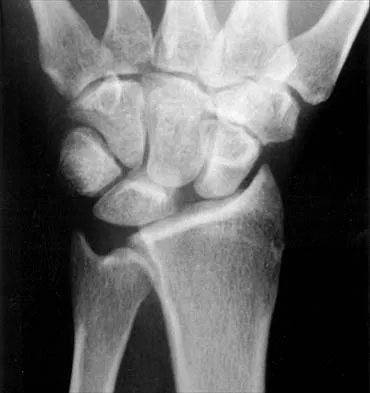

Figures 45a and 45b show the radiographs of a 14-year-old boy who sustained a distal radius fracture while playing hockey. After 1 year the patient is asymptomatic. Follow-up and comparison radiographs and an MRI scan are shown in Figures 45c and 45d. What is the next most appropriate step in management?

The patient sustained a growth plate fracture of the distal radius and ulna. Although treated with closed reduction and casting, the follow-up radiographs demonstrate shortening of the radius in comparison to the ulna, and the MRI scan confirms thinning of the distal radius growth plate and bony bars consistent with a growth arrest. At this time, the discrepancy in length is too minor to consider lengthening of the radius; in addition, excision of a physeal bar with minimal growth potential is not likely to restore the gross discrepancy. Ulnar styloid fractures are rarely symptomatic and do not require treatment in the asymptomatic patient. Closure of the distal ulna growth plate will prevent further discrepancy between the radius and ulna. Vanheest A: Wrist deformities after fracture. Hand Clin 2006;22:113-120.